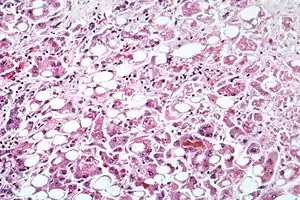

Hepatita este o boală infecțioasă de natură virală, microbiană sau toxică a ficatului care constă în distrugerea celulelor hepatice. Există mai multe forme ale bolii ca: Hepatită A, Hepatită B, Hepatită C, Hepatită D, Hepatită E, Hepatită F, Hepatită G. Indiferent de agentul cauzal, boala se manifestă la început prin simptome nespecifice, uneori febră ușoară, lipsa apetitului, emeză (grețuri, vomitări), scăderea randamentului fizic și psihic, ca și dureri abdominale, urina devine de culoare închisă, fecalele de culoare deschisă și apar forme icterice. Boala produce de regulă în final ciroză, sau cancer de ficat. După incindența bolii, România se află printre primele locuri în Europa, din cauza costului ridicat al tratamentului, conform programului Casei Naționale de Sănătate, numai 1% din bolnavi sunt tratați cu medicație antivirală.[3]